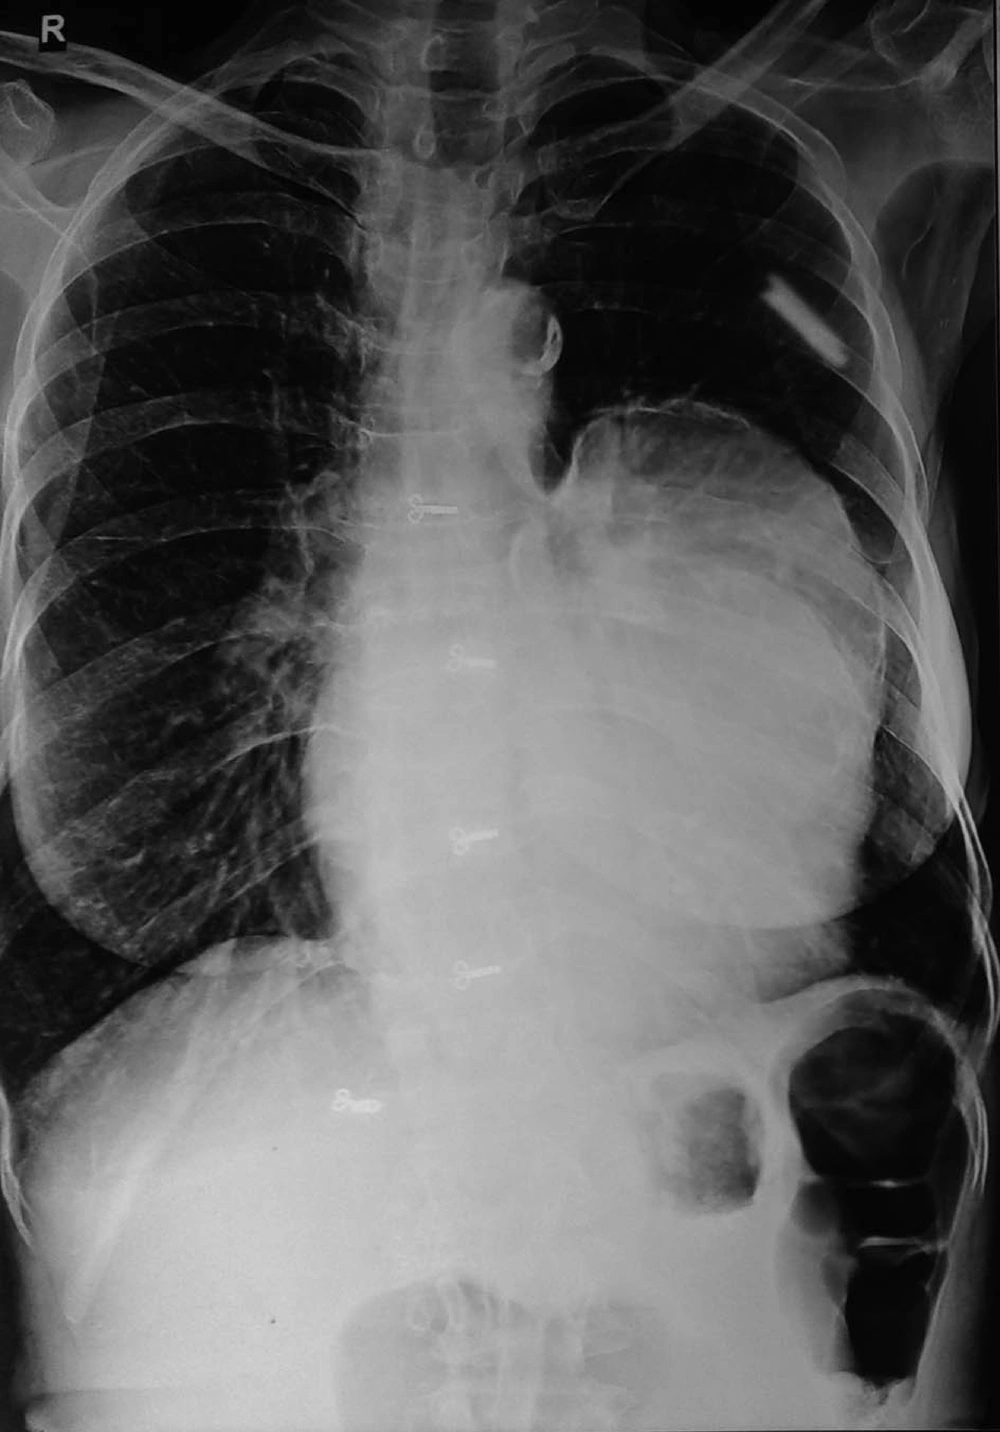

In June 2011, a 60 year old woman was admitted to our emergency room with complaints of shortness of breath, palpitation, chest pain and progressive dyspnea. She had history of dyspnoea on exertion and orthopnea too. She had no history of trauma or major illness. On her physical examination, arterial blood pressure was 135/90 mmHg, heart rate was 110 beats per minute, SpO2 94% on room air and respiratory rate was 24 breaths per minute. On auscultation, the lungs were normal and no cardiac murmur, no JVP raised or gallop rhythm was noted. Cardiac enzymes, biochemical analysis, and complete blood count were normal except for eosinophilia. Chest radiography noted that cardiomegaly with bulging left heart boarder at admission (Figure 1). Electrocardiography (ECG) showed normal sinus rhythm with poor progression of R wave in lead v4, v5, and v6 and no changes in ST segment. Her myocardial-specific enzyme values were found in the normal range. Transthoracic echocardiographic investigation showed a large multicystic mass (size 77 × 57 mm) seen intrapericardially extending from left ventricle lateral wall to pericardial sac causing pressure effect on left ventricle. The abdominal ultrasonography revealed intracardiac hydatid and other cystic lesion either in the liver or other abdominal organs were not found. Contrast-enhanced CT confirmed the presence of a well-defined, thin-walled, homogeneous multiple cardiac hydatid cyst with internal trabeculae arising from pericardium with adjacent structure (Figure 2). Results of serologic tests for hydatidosis (indirect hemagglutination tests) were positive for E. granulosus, and marked eosinophilia was present too. After diagnosis, the patient was scheduled for surgery with the diagnosis of cardiac hydatid cyst. Patient was taken into the operation theatre and monitoring including ECG, pulse oximetry and non-invasive blood pressure were established and general anesthesia was performed with opioid-muscle relaxant technique after that established left radial artery cannulation for beat to beat blood pressure monitoring and internal juglar vein cannulation for central venous pressure monitoring. The pericardium was accessed through left lateral thoracotomy, accessing to the left mediastinal area, a solitary cystic lesion with a well-defined border was visualized in the pericardium adjacent to the left ventricle and the pericardial cyst was surgically removed (Figure 3). Patient’s trachea extubated and Intraoperative and postoperative hemodynamic status was maintained and within normal limits. Post-operative pain managed with inter costal block with 0.5% of bupivacain plain, inj. tramadol and diclofenac sodium I.M. Pathologic examination of the specimen was shown with hydatid cyst.